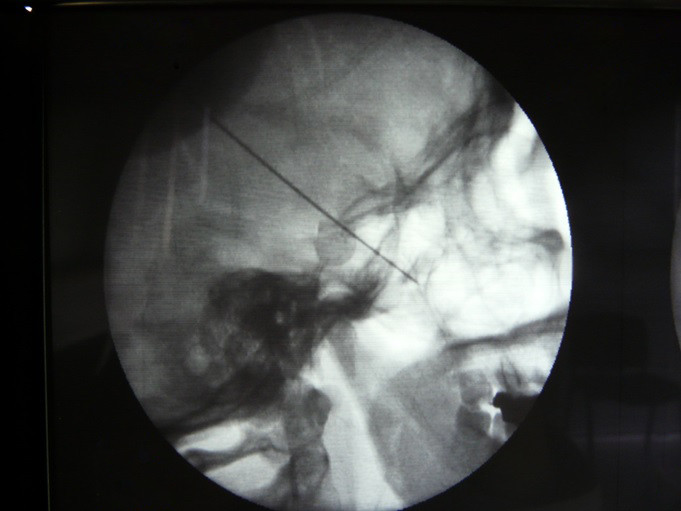

Fig.3. En esta proyección Antero posterior se observa la punta de la aguja a nivel del cornete medio, dónde el Ganglio Esfenopalatino se sitúa muy próximo a la mucosa del cornete medio, por lo que es de suma importancia introducir la aguja , la crio sonda o el electrodo en la proyección AP para no perforar la mucosa nasal.